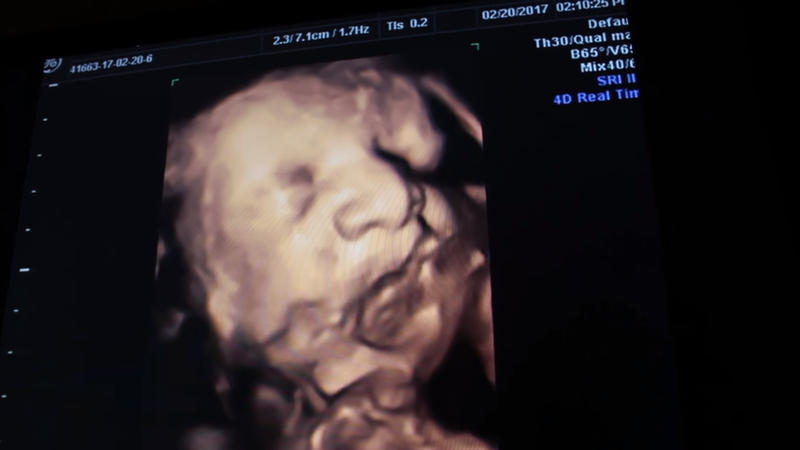

With only a couple of months left of Katie’s pregnancy, the couple found out that one of the babies was endangered because of the fact that it wasn’t getting enough fluid. As a result of this, the baby was significantly smaller than the other two.